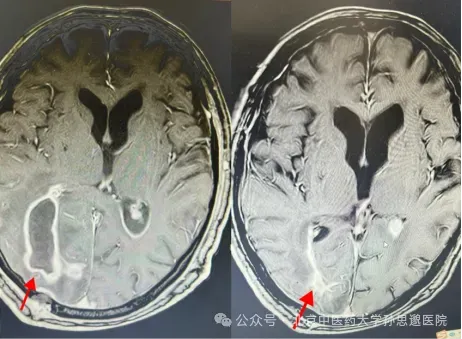

CT示脑脓肿破入脑室,术后脑室积极脓彻底清除

术前、术后脑脓肿彻底清除(图中剪头所指)